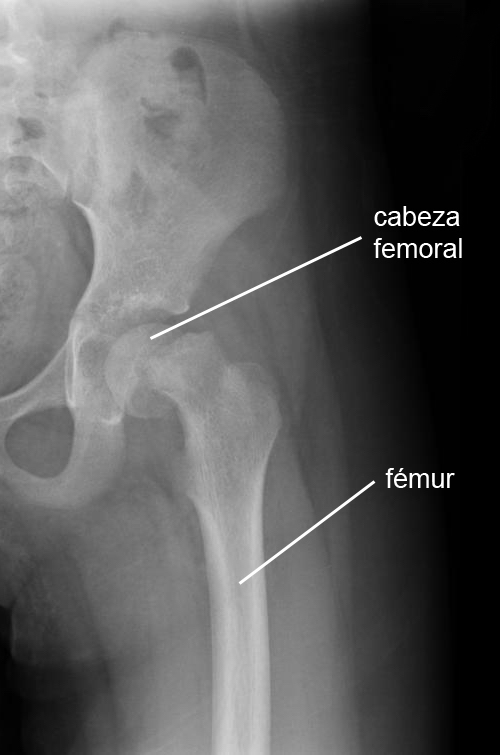

El deslizamiento de la epífisis femoral capital (SCFE) es un problema de cadera que se produce cuando la cabeza del fémur (hueso del muslo) amenaza con separarse del fémur. Esta enfermedad afecta a niños de entre 8 y 17 años. Puede ocurrir en una pierna, pero también puede afectar a ambas. El diagnóstico suele pasarse por alto en los niños.

El deslizamiento de la epífisis femoral capital se produce con frecuencia en un período de rápido crecimiento, poco después de comenzar la pubertad. Por razones que aún no están claras, el cartílago de crecimiento situado entre la cabeza del fémur y el fémur se debilita. Esto hace que el fémur se desplace hacia arriba y hacia delante en relación con la cabeza del fémur. Puede tratarse de una afección aguda o crónica.

El diagnóstico se realiza mediante radiografías.

La cabeza del fémur se fija quirúrgicamente al fémur para evitar que siga deslizándose hacia fuera, hasta que el cartílago de crecimiento se haya fusionado y osificado.